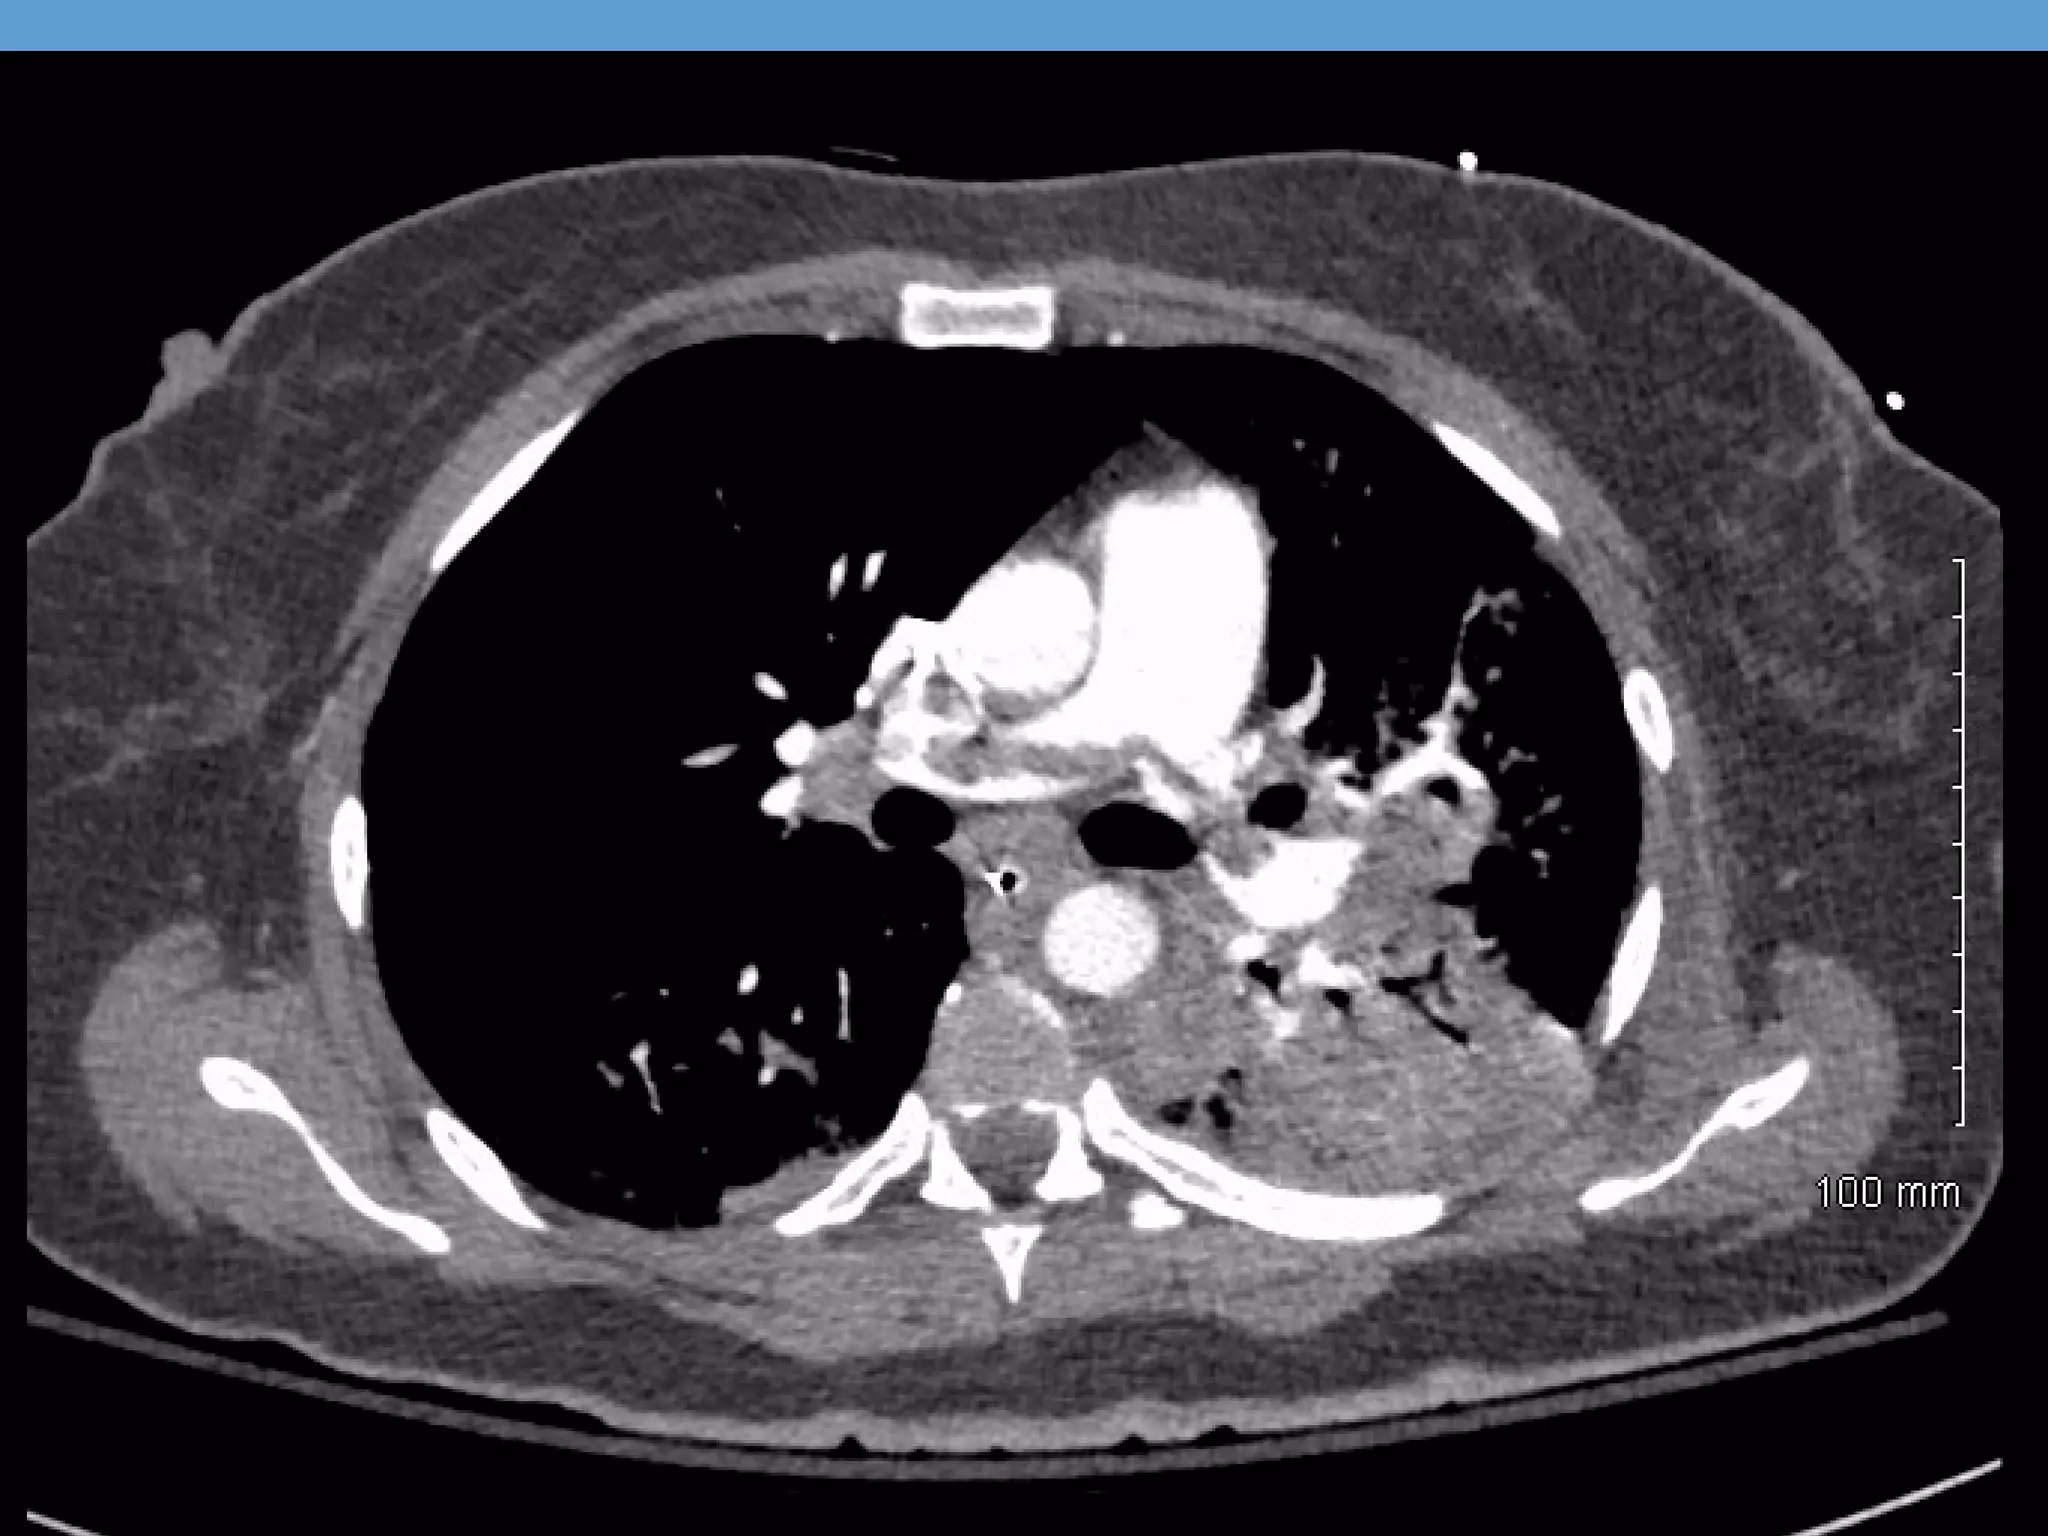

CT PE Protocol

CT CHEST W CONTRAST (PE) PROTOCOL 11/1/2013

Findings: Opacification of the pulmonary vasculature is

good. There is a saddle embolus with clot extending

predominantly into the lower lobe pulmonary arteries, with

the most significant clot burden in the left lower lung.

Additional regions of emboli are seen in the right middle

lobe There is evidence of right heart strain with a right

ventricle to left ventricular ratio of greater than 1.

CT PE Protocol CTCHEST W CONTRAST (PE) PROTOCOL 11/1/2013 1:01 PM Findings: Opacification of the pulmonary vasculature is good. There is a saddle embolus with clot extending predominantly into the lower lobe pulmonary arteries, with the most significant clot burden in the left lower lung. Additional regions of emboli are seen in the right middle lobe There is evidence of right heart strain with a right ventricle to left ventricular ratio of greater than 1.